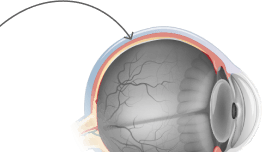

ciliary body

iris

anterior chamber

pupil

cornea

lens

ora serrata

medial rectus

vena

optic nerve

artery

vitreous

macula

retina

sclera